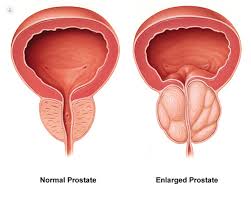

Sexual impotence could cause problems with interpersonal associations, in addition to lower a singleÂ’s self impression and self-self confidence. Very often, sexual impotence provides rise to extreme despair and psychological trauma, While in others, psychological aspects could be the reason for impotence. The main detail to do is tackle the condition at the earliest. If this is finished, in several situations, there may well not even be a need for any kind of clinical intervention.

Thankfully, treatment options are offered for ED. They can be generally Risk-free and successful in about 70% of situations.